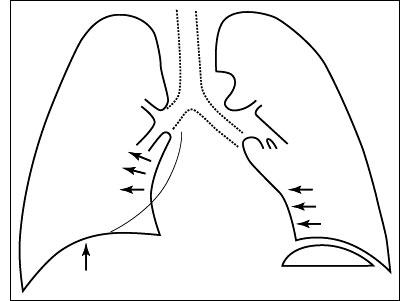

ESQUEMA 17 Comentario placa 17 Detrás del corazón se distingue una sombra triangular paravertebral que corresponde al lóbulo inferior derecho colapsado. Aunque no se viera esta imagen directa del lóbulo retraído, la existencia de la atelectasia sería detectable por el desplazamiento del corazón hacia la derecha y el ascenso diafragmático. Pase a la placa 18 que corresponde al mismo paciente unas pocas horas después de haberse aspirado broncoscópicamente un gran tapón mucoso que ocluía el bronquio del lóbulo inferior derecho. Observe la desaparición de la condensación retrocardíaca y la corrección de los desplazamientos del diafragma y mediastino. |